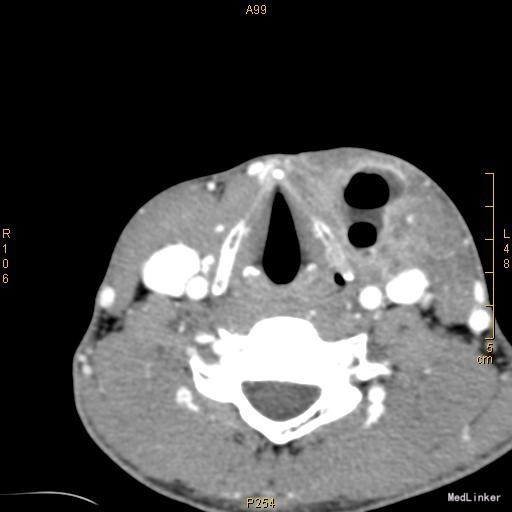

查体:颈前有明显手术瘢痕,左侧颈外侧区可触及一约3cm×3cm大小肿物,质韧,边界不清,表面光滑,不可随吞咽上下移动,触痛明显,颈部未闻及明显血管杂音。 辅查:2015-11-16我院颈部增强CT示左侧颈部感染,多发脓肿形成。

该患者在诊断上是有些困难,颈部多发脓肿是明确的,但是瘘口的位置不好确定,从而未能确诊,8年前患者行上消化道钡餐检查,诊断“食管瘘”,但是我们从8年前的影像上看,瘘口的位置太高,不像是食管的瘘口,考虑是不是梨状窝的瘘道,为了进一步确诊,我们给患者行了胃镜检查,结果胃镜发现左侧梨状窝有1个3mm大小的小孔,胃镜未能通过,食管未见明显的瘘口。为了更加明确瘘口的位置,我们与影像科商议后决定口服造影剂后行颈部CT平扫,因怕钡餐沉积在脓肿内不好排出,我们采用了口服碘化油。此次影像明确了瘘口的确在左侧梨状窝。最终诊断:左侧颈部多发脓肿;左侧梨状窝瘘道形成。 治疗:入院后予抗感染、禁食、营养支持等治疗,患者感染得以控制,请耳鼻咽喉科会诊后建议转科治疗。